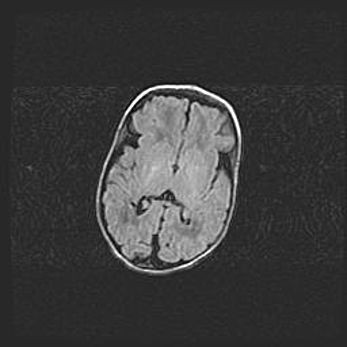

Наружная гидроцефалия с возможной атрофией височных областей.

Возраст: 28 дней

Вес: 3670 г

Пол: мужской

Окружность головы: 38 см

Срок гестации: 40 недель

Гидроцефалия головного мозга у новорожденных – это заболевание, которое характеризуется скоплением избыточного количества спинномозговой жидкости в желудочковой системе головного мозга в результате затруднения её перемещения от места выработки к месту поглощения в кровеносную систему или вследствие нарушения абсорбции. При открытой наружной форме гидроцефалии у новорожденных расширяются и переполняются субарахноидные пространства.

При нормотензивных  формах,  которые,  как  правило,  являются  следствием  перенесенных ишемических  повреждений  паренхимы  мозга,  возможно  сочетание микроцефалии  с нормотензивной гидроцефалией. В основе данных изменений лежит атрофия больших полушарий с преимущественной  локализацией  в  лобно-височных  областях.